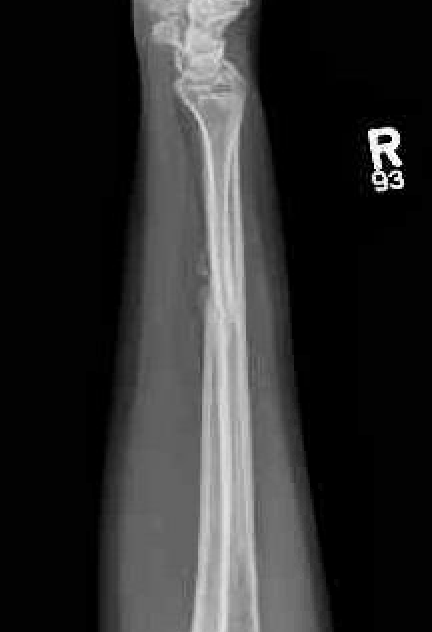

Nonunions

Results

- IM K wire v plate in 54 patients

- 3 nonunions with plate, none with IM wire

- 70% of patients required wire removal

- 11% of patients required plate removal

Ulna nonunion after plating